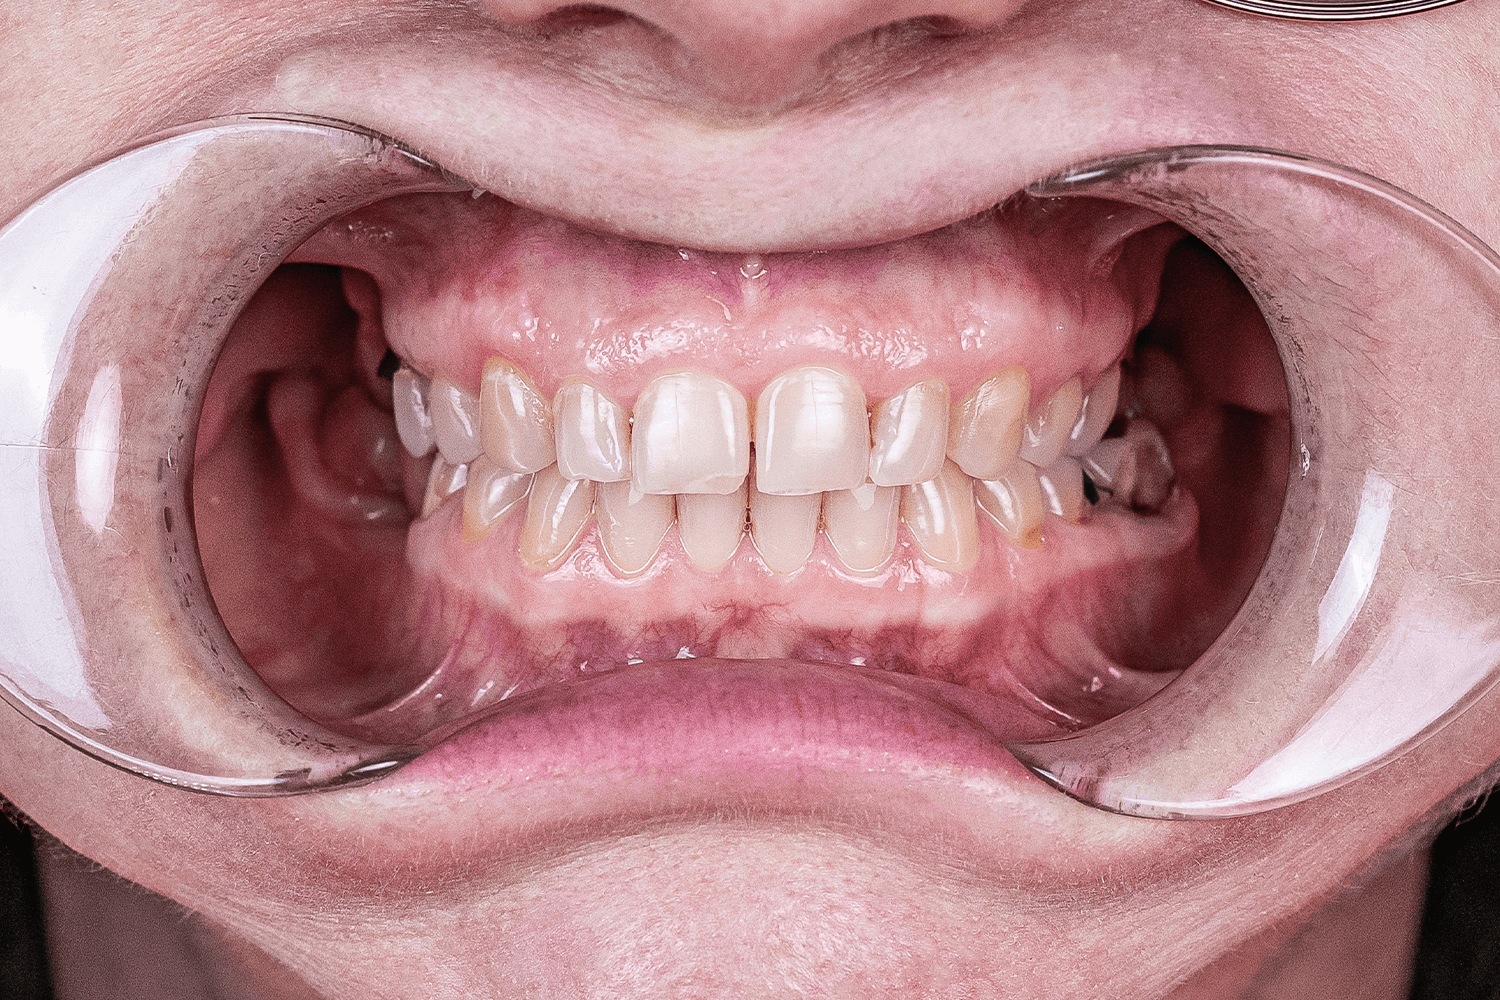

- покрыть зубы керамическими коронками и винирами и сразу поднять прикус ортопедическим методом.